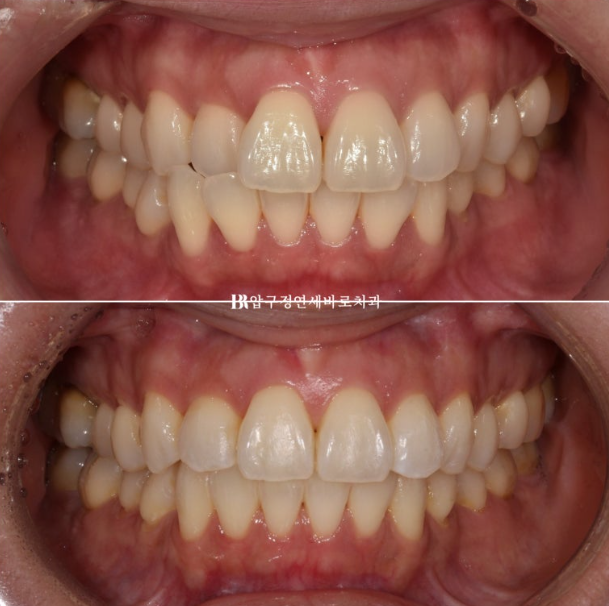

Let me introduce orthodontic treatment for anterior crossbite and buck teeth.

23.10

The blue arrow shows the front teeth biting in the wrong direction.

Because the teeth that bite in the wrong direction are positioned backward, the two central incisors appear relatively protruded.

24.01

This is the appearance in the fourth month after treatment began.

Interproximal reduction was also performed for front-tooth alignment, and auxiliary appliances and elastic bands were used to eliminate the spaces that formed.

After 4 months of treatment, we finally completed treatment in January 2024.

Left - Before treatment / Right - After treatment

23.10~24.01